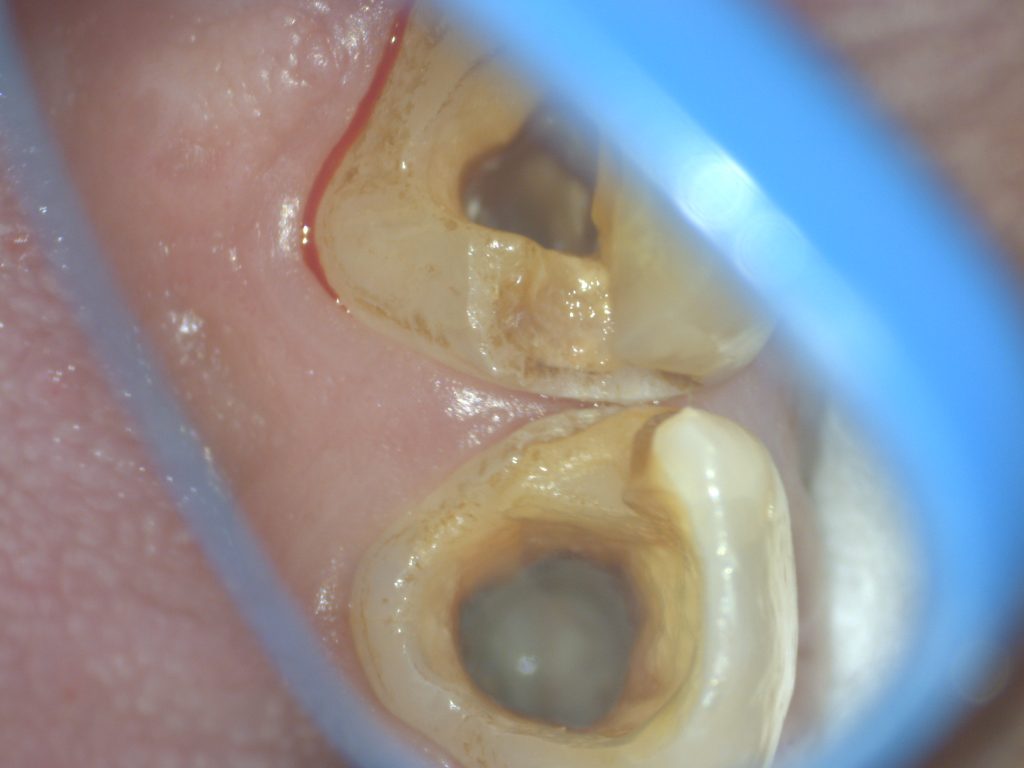

先日、初診で見えた患者さんですが3年前に根管を開放してそのままの状態で経過してお見えになりました。

3年間の長期にわたり根管を開放してしまうと予後は明らかに悪くなります。残念ながら見通しは明るくはありません。

しかしながら、この療法は注意が必要です。根管が外の世界に露出されるので口腔内の細菌が歯の中に侵入してきます。

長期間根管を開放した場合、予後が悪いのは明らかです。